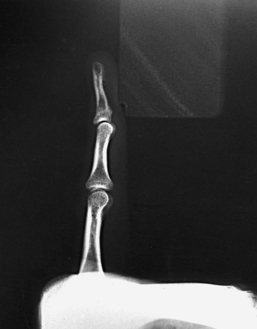

Structures shown: A lateral projection of the affected digit is shown (Figs. 4-24 through 4-27).

• Because lateral digit positions are difficult to hold, tell the patient how the digit is adjusted on the IR and demonstrate with your own finger. Let the patient assume the most comfortable arm position.

• Ask the patient to extend the digit to be examined. Close the rest of the digits into a fist and hold them in complete flexion with the thumb.

• Support the elbow on sandbags or provide other suitable support when the elbow must be elevated to bring the digit into position.